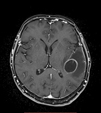

Ascesso

cerebrale |